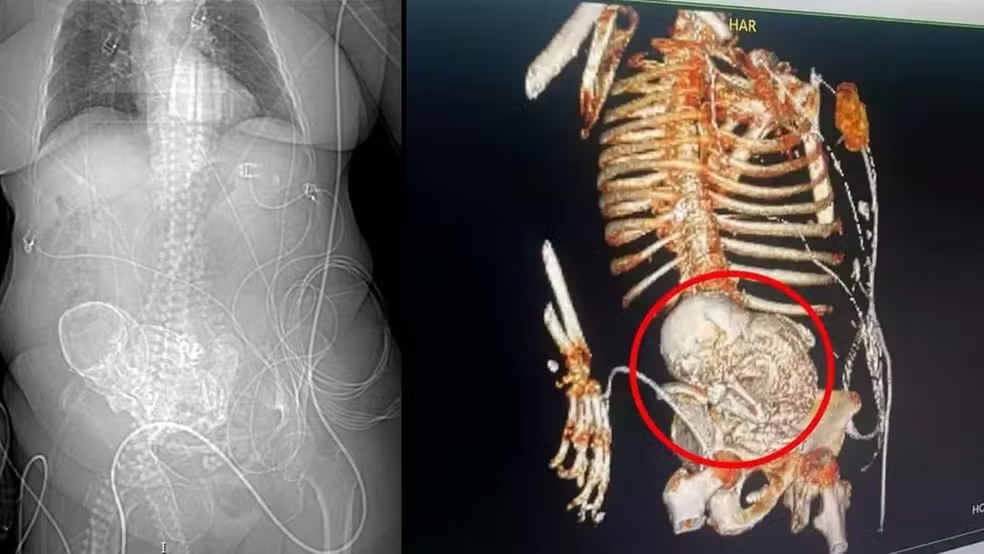

Idosa de 81 anos descobre feto calcificado que carregou por mais de 5 décadas

Feto calcificado 19/03/2024 - 14h14 Idosa de 81 anos descobre feto calcificado que carregou por mais de 5 décadas A suspeita da equipe médica é de que a mulher estava com o feto calcificado no abdômen há 56 anos, desde quando a idosa teve a última gestação. A idosa morreu logo após cirurgia para retirada do feto.